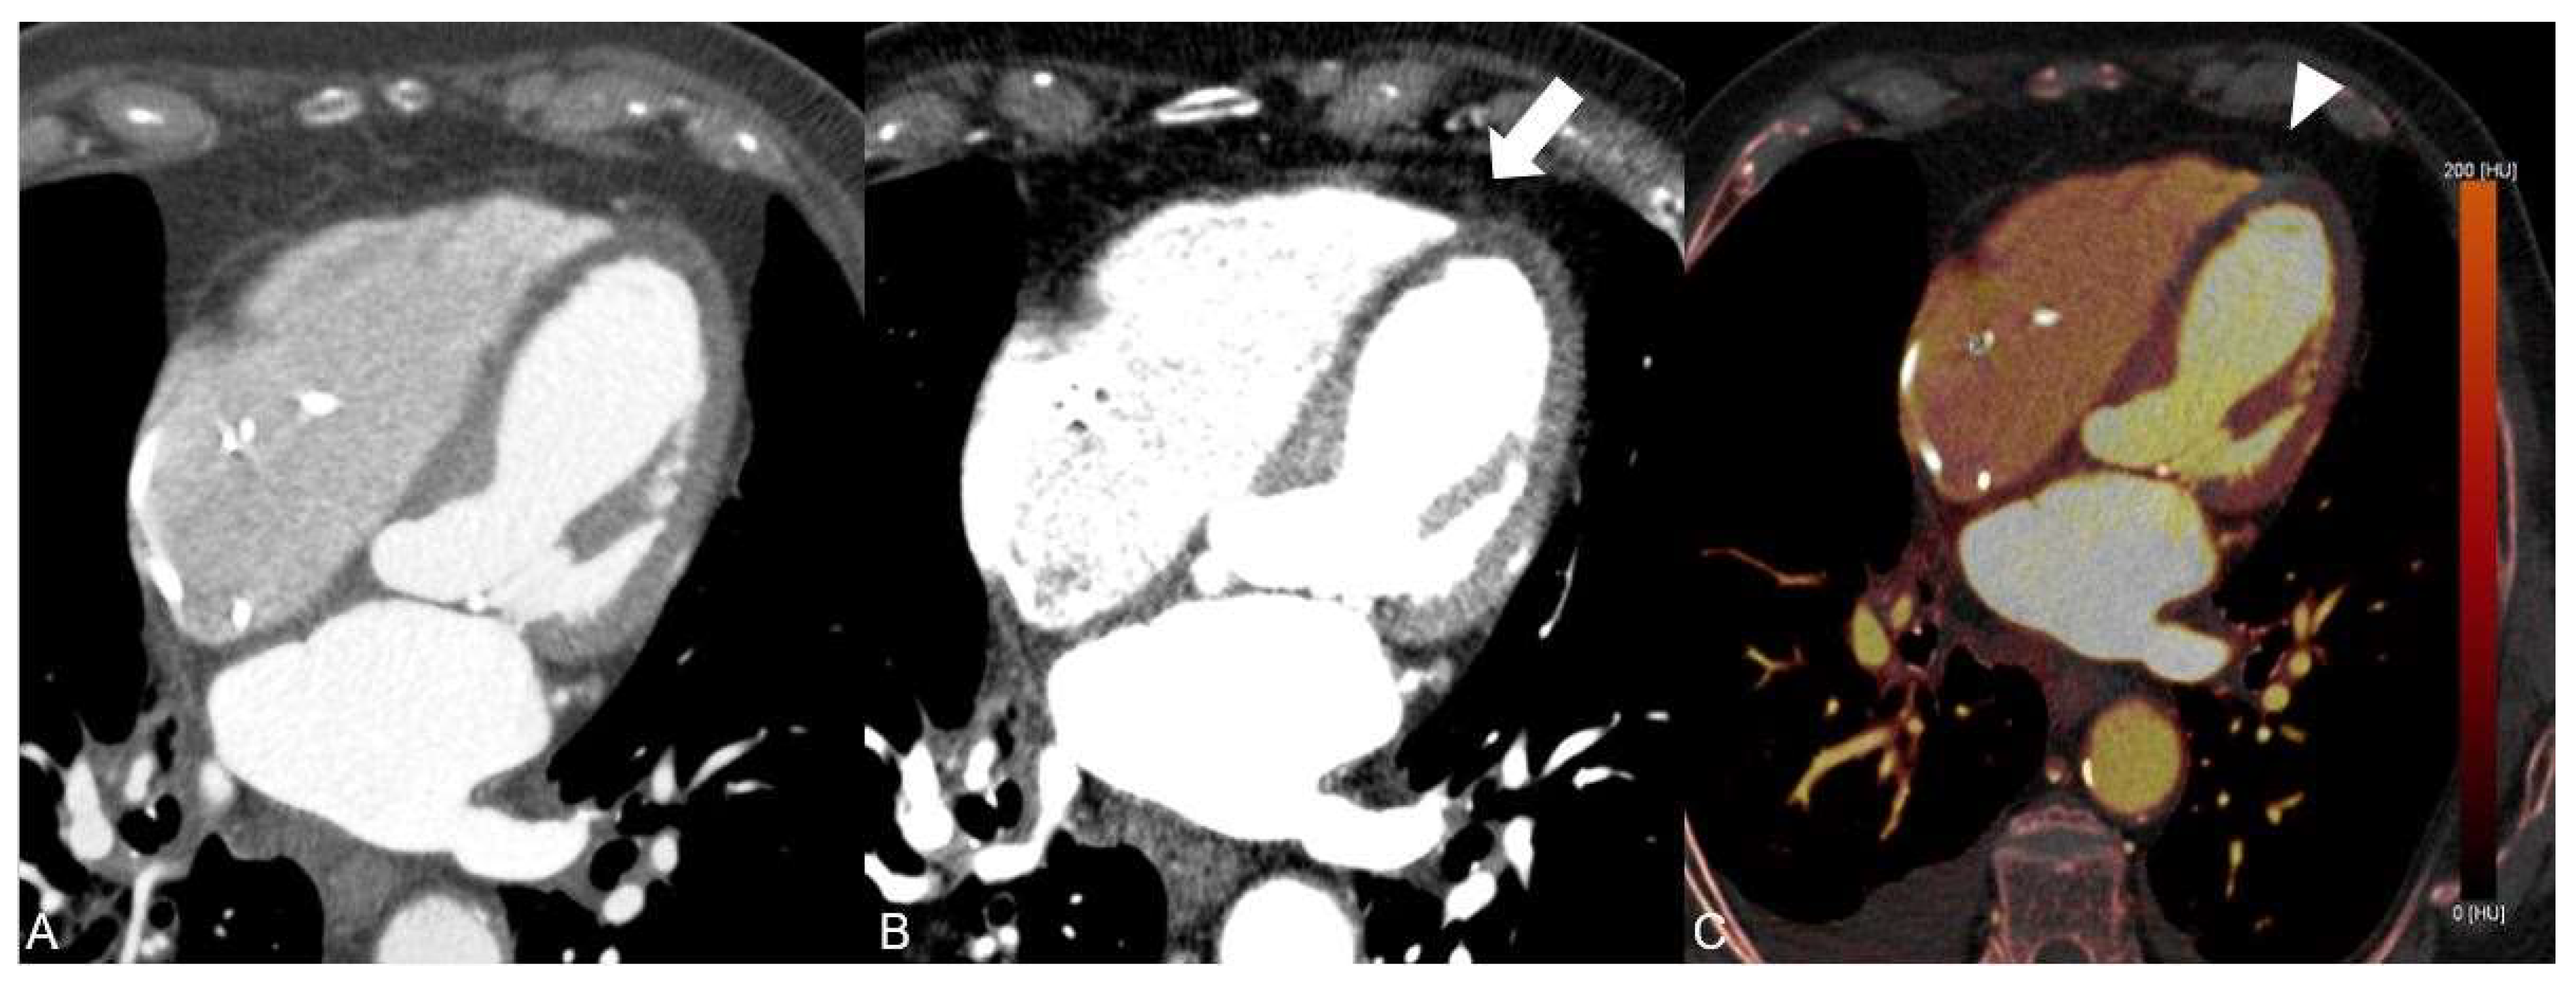

Furthermore, the DECT-based iodine maps demonstrated significant hypoperfusion of the anterior wall and anterior septum suggestive for an acute anterior wall infarction, which was missed on conventional CT series (Figure 3). Pulmonary artery embolism and aortic dissection were excluded.

Figure 3. Significant hypoperfusion of the anterior wall and anterior septum is visible and can be quantified on dual-energy CT iodine maps using the four chamber view (A) and short axis view (B) indicating acute myocardial infarction in this area due to the LAD occlusion.